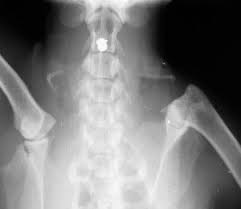

Enlarged Kidney X Ray. Hydronephrosis can occur in one or both kidneys. Because kidney enlargement often causes no symptoms it is often discovered incidentally on an imaging study such as an an abdominal ultrasound x ray or ct scan.

Normal kidney size in adults. Generally kidney enlargement is a symptom of an underlying disease or disorder of the kidneys. My dog was diagnosed with enlarged kidneys after and x ray and ultrasound.

Treatment of an enlarged kidney will often involve recognizing and treating the underlying condition. The normal reference range sizes for kidneys are 2 5 3 5 x the length of l2 for dogs and 2 3 x the length of l2 for cats. The kidneys the ureters the bladder and urethra. Hydronephrosis can occur in one or both kidneys.